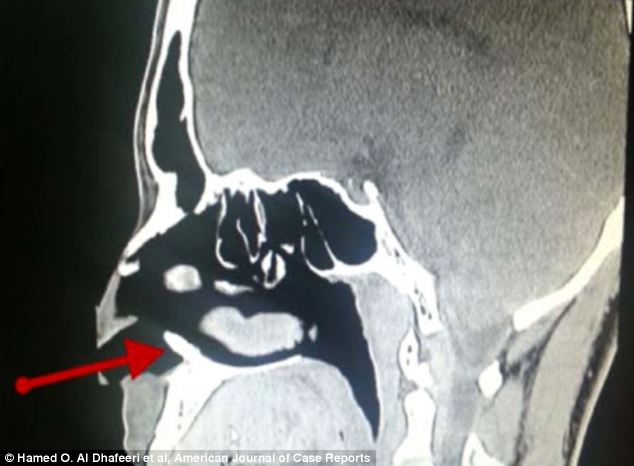

Scan adanya gigi yang tumbuh sampai ke hidung.

Penemuan gigi tersebut sangat mengejutkan karena pria tersebut memiliki gigi yang lengkap dan tersusun rapi dalam mulutnya. Gigi ekstra ditunjukkan pada CT scan ini, ditandai dengan panah merah